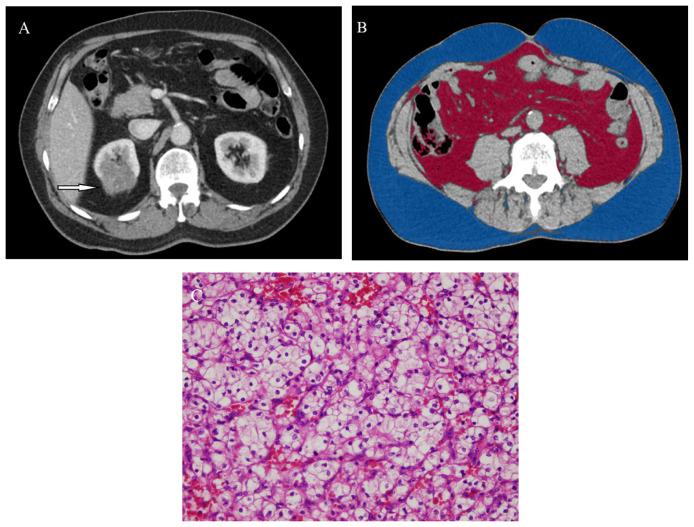

BACKGROUND/AIM: To investigate the relationship between sex-related visceral obesity and WHO/ISUP nuclear grade in clear cell renal cell carcinoma (ccRCC).

Between January 2018 and June 2022, 95 patients (56 men and 39 women) with pathologically proven ccRCC who underwent abdominal computed tomography examination were retrospectively examined. The patients were classified into two groups: low- and high-WHO/ISUP nuclear grade ccRCC (n = 58 and n = 37), respectively. Patient height, weight, body mass index (BMI), sex, age, subcutaneous fat area (SFA), visceral fat area (VFA), total fat area (TFA), and percentage of visceral fat (VF%) were recorded for the two groups.

No significant differences were found in age, BMI, SFA, or TFA, but VFA and VF% were significantly higher in the high-grade patient group. In males, maximal tumor diameter (MTD) (67.8% sensitivity and 76.9% specificity) had the highest area under the curve (AUC), while in females, VF% (70.0% sensitivity and 73.7% specificity) had the highest AUC. VF% revealed an odds ratio (OR) of 1.09 in females with high-grade ccRCC, and in males, MTD was an independent predictor of ccRCC with an OR of 1.03.

Sex-related body fat tissue, including VFA and VF%, could be used for estimating WHO/ISUP nuclear grade in patients with ccRCC, especially in females.